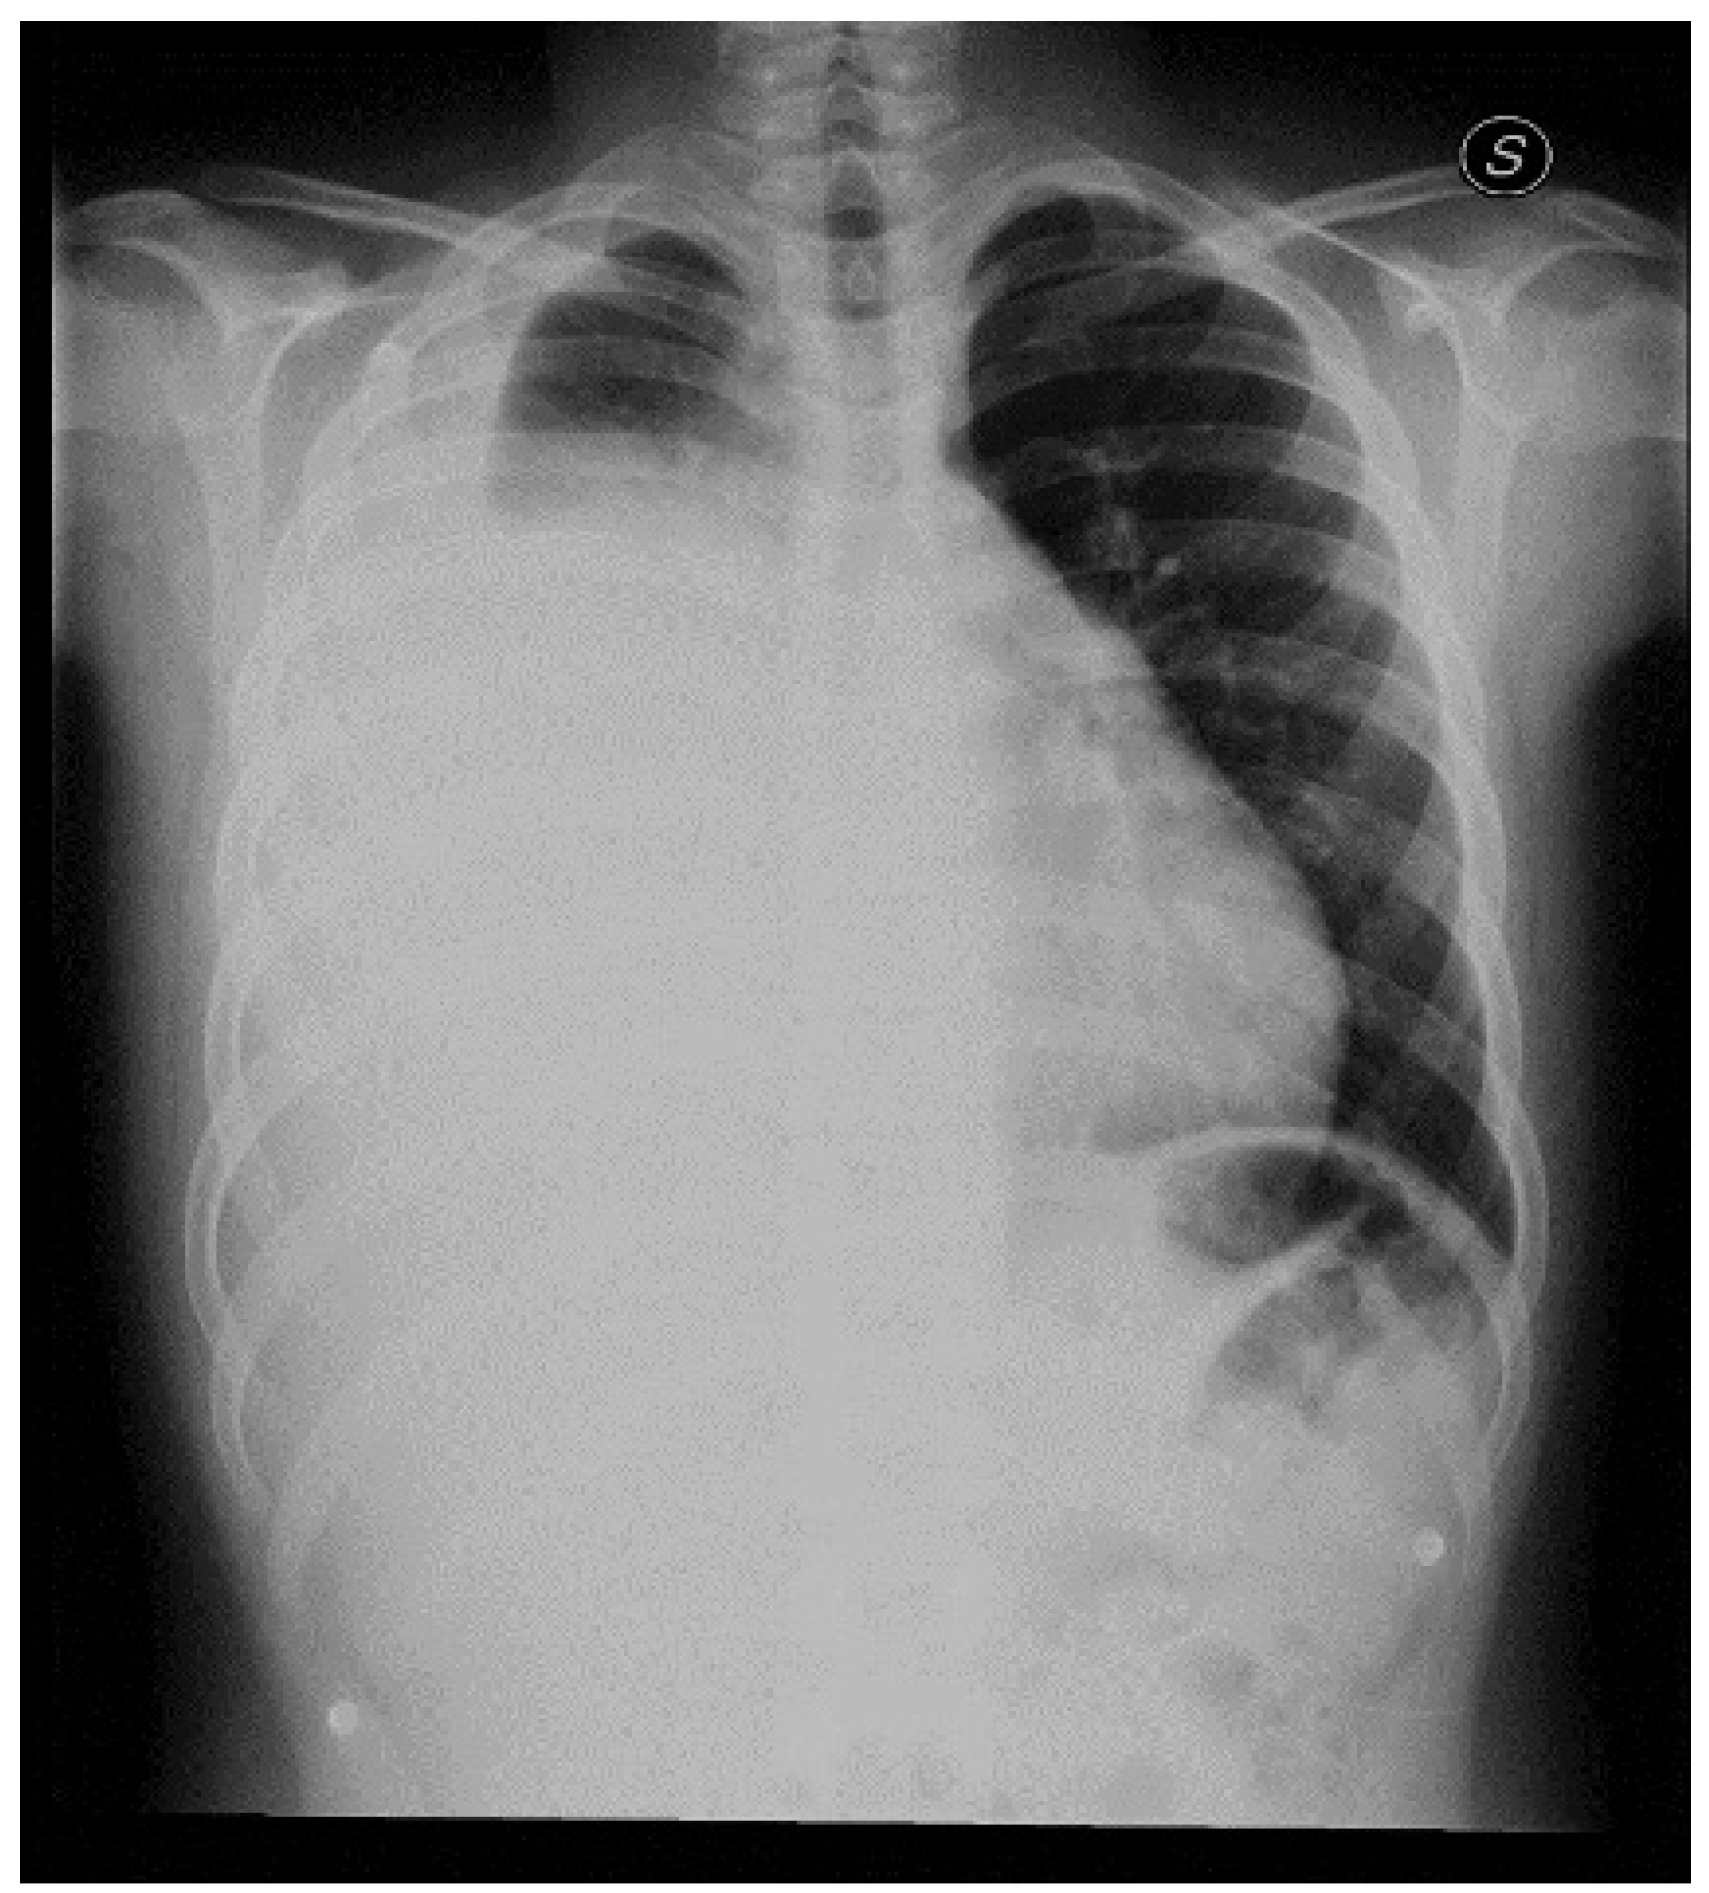

The Key Role of Lung Ultrasound in the Diagnosis of a Mature Cystic Teratoma in a Child with Suspected Difficult to Treat Pneumonia: A Case Report

2. Case Report